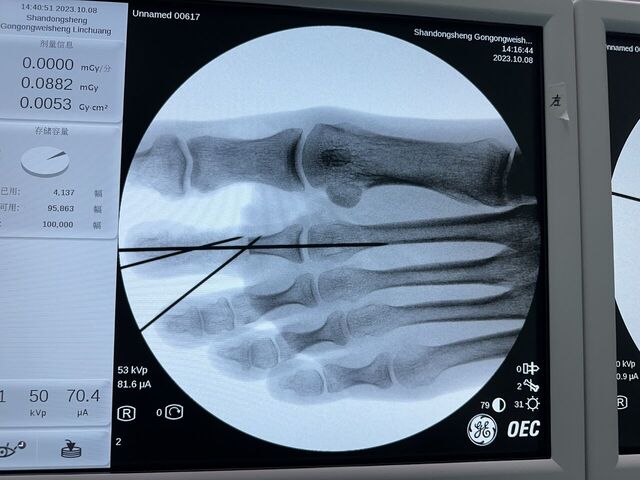

示指再造 1.5月随访

微信图片_20231011185314.jpg 微信图片_20231011185317.jpg 微信图片_20231011185255.jpg 微信图片_20231011185259.jpg 微信图片_20231011185303.jpg 微信图片_20231011185310.jpg 微信图片_20231011185557.jpg 微信图片_20231011185307.jpg